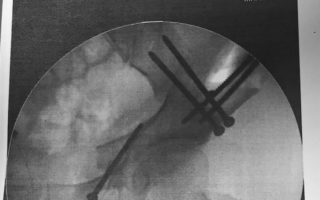

Heute kommt hierzulande aber auch eine zweite OP-Methode standardmäßig zum Einsatz: die Periazetabuläre Osteotomie (PAO). Inzwischen haben sich viele Kliniken in Deutschland, Österreich und der Schweiz auf dieses Verfahren spezialisiert. Die PAO hat ebenfalls die Neuorientierung der Hüftpfanne zum Ziel, aber anders als bei der Triple-Osteotomie erfolgen die Knochenschnitte um die Hüftpfanne herum („periazetabulär“). Sitzbein und Darmbein werden nicht vollständig durchtrennt, der hintere Beckenring bleibt bei der PAO intakt.

Prof. Dr. med. Henning Windhagen: Die PAO ist der schnellere Eingriff. Die Operation ist kürzer und geht aufgrund der geringeren Zeit mit weniger Blutverlust einher. Anders als bei der Triple-Osteotomie müssen wir den Patienten oder die Patientin während der OP nicht umlagern. Allerdings ist die Periazetabuläre Osteotomie auch schwerer zu operieren. Bei der Dreifachen setzt man drei glatte Schnitte „geradeaus“. Bei der PAO setzt man einen Kantenschnitt und muss ertasten, wo man meißeln muss.